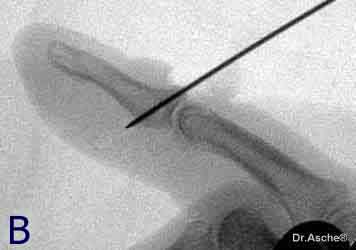

Zunächst wird das kleine Fragment exakt reponiert

und mit einem 0,8 mm K-Draht fixiert. Der Draht muß exakt in der

Mitte des Fragmentes liegen.